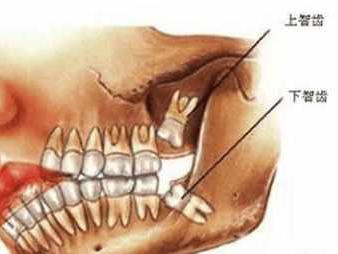

Jun 30, 21 · 通常情况,会有上下左右4颗智齿萌出 ;但也有的人会少于4颗,甚至不长 (这可能是因为天生缺失智齿牙胚,或者埋在牙槽骨里不萌出) ; 萌出时间: 智齿 一般会在16岁~25岁期间萌出 ,也有人会在三四十岁左右才萌出智齿。 那么,智齿到底要不要拔? 不Sep 26, 19 · 拔牙后五天,依然肿胀,正常吗?01 为什么有的人拔牙后肿成「猪头」?其实,拔牙后的肿胀是非常常见的,尤其是下颌的智齿,由于拔牙创伤相对较大,术后的肿胀也比上颌智齿拔除后要更智齿肿的时候能拔吗 网 : 牙齿周围已经发炎红肿,是不适合进行拔牙的,因为这样的话,会增加损伤的面积,极易造成感染、出血等异常表现这种情况应该是先进行抗菌治疗,如炎可宁、甲硝唑芬布芬胶囊等药物的使用,等炎症消退后再进行拔牙的治疗,牙龈发炎期不能拔牙,要等消炎完才可以,等消炎